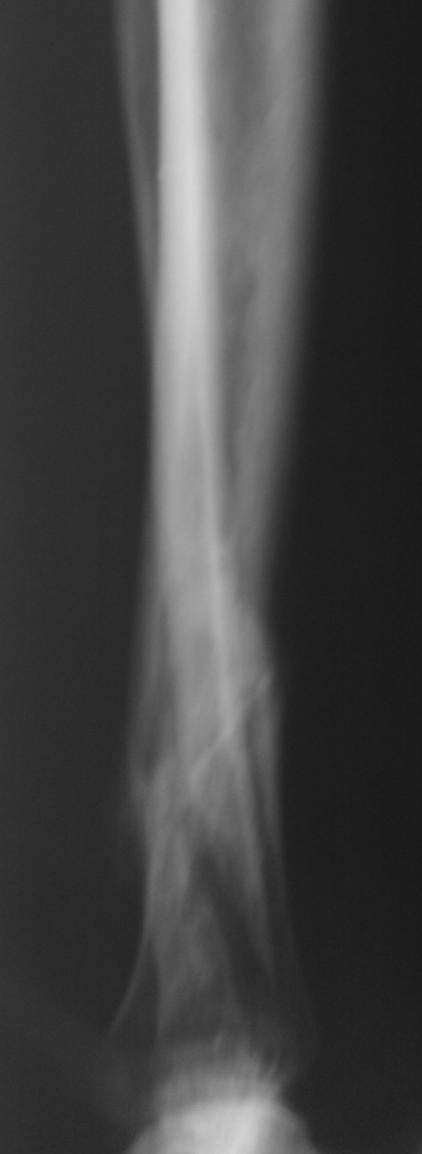

пример функционального лечения по Сармиенто похожего перелома. Рентгенограммы в 1 мес, 3,5 мес, фото и видео 3,5 мес. Движения в колене в полном объеме, в голеностопе - небольшое ограничение (пара дней после снятия повязки), нагрузка безболезненная.

Уважаемый Максим. Я бы постеснялся выставлять такие снимки. Во-первых потому, что давно считается аксиомой: нельзя лечить нестабильные переломы консервативными методами. Во-вторых кость срослась в положении поперечного смещения на 1/3 диаметра, нарушена биомеханическая ось, а это аукнется на суставах. В-третьих, консолидация достигнута в положении укорочения 1-1,5 см. По предложенной нами шкале оценок исходов лечения данный исход тянет в лучшем случае на удовлетворительную оценку.